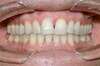

Vues avant le traitement

Vues après le traitement